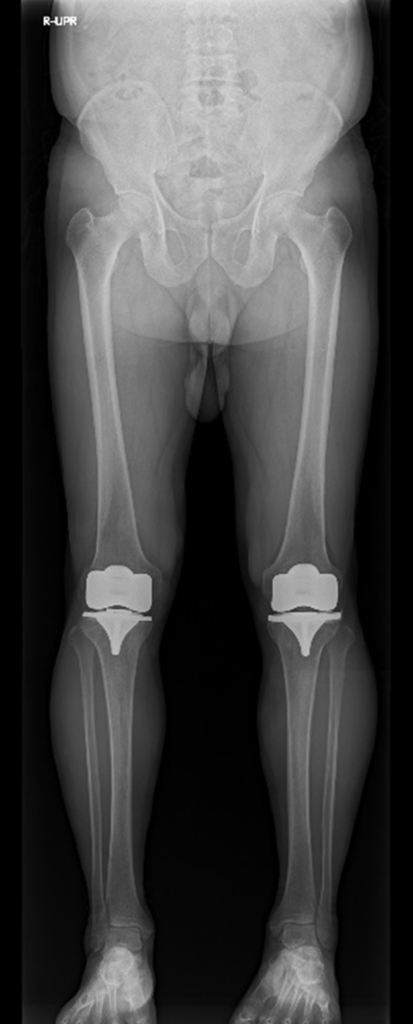

レントゲン検査では整形外科の患者数が多く、全脊椎や下肢全長を撮影する検査も増加傾向にあります。当院では DR CALNEO GL(FUJIFILM 社製)を導入しており、より短時間・低線量の長尺撮影が可能となっています。

DR CALNEO GL

全脊椎

下肢全長